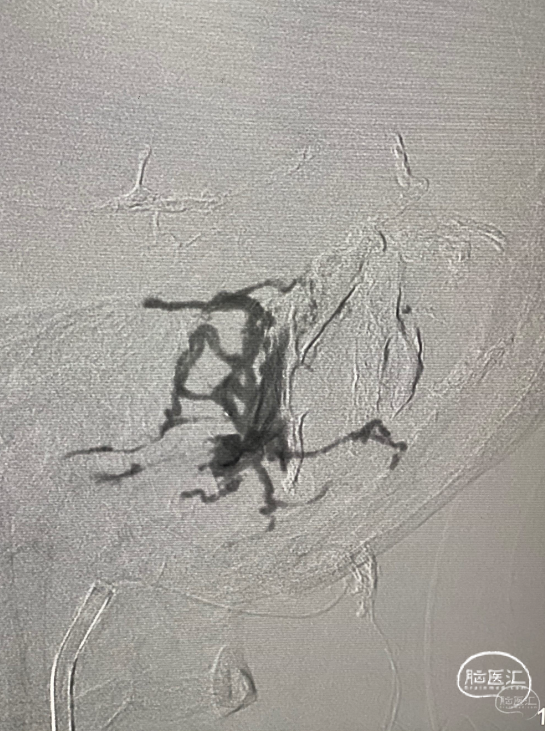

第三台,一个侧窦区的硬脑膜动静脉瘘,供血动脉繁多,以前的栓塞让脑膜中动脉的路径给用掉了。

栓塞路径都不好,枕动脉供血动脉里面挑选出一支,经过努力,很好的到达了瘘口。

接着的事情就是往里面打栓塞剂。

继续打,直到将瘘口完全闭塞。

再次造影,那些繁杂的血管消失了,瘘口得到了很好的解决。